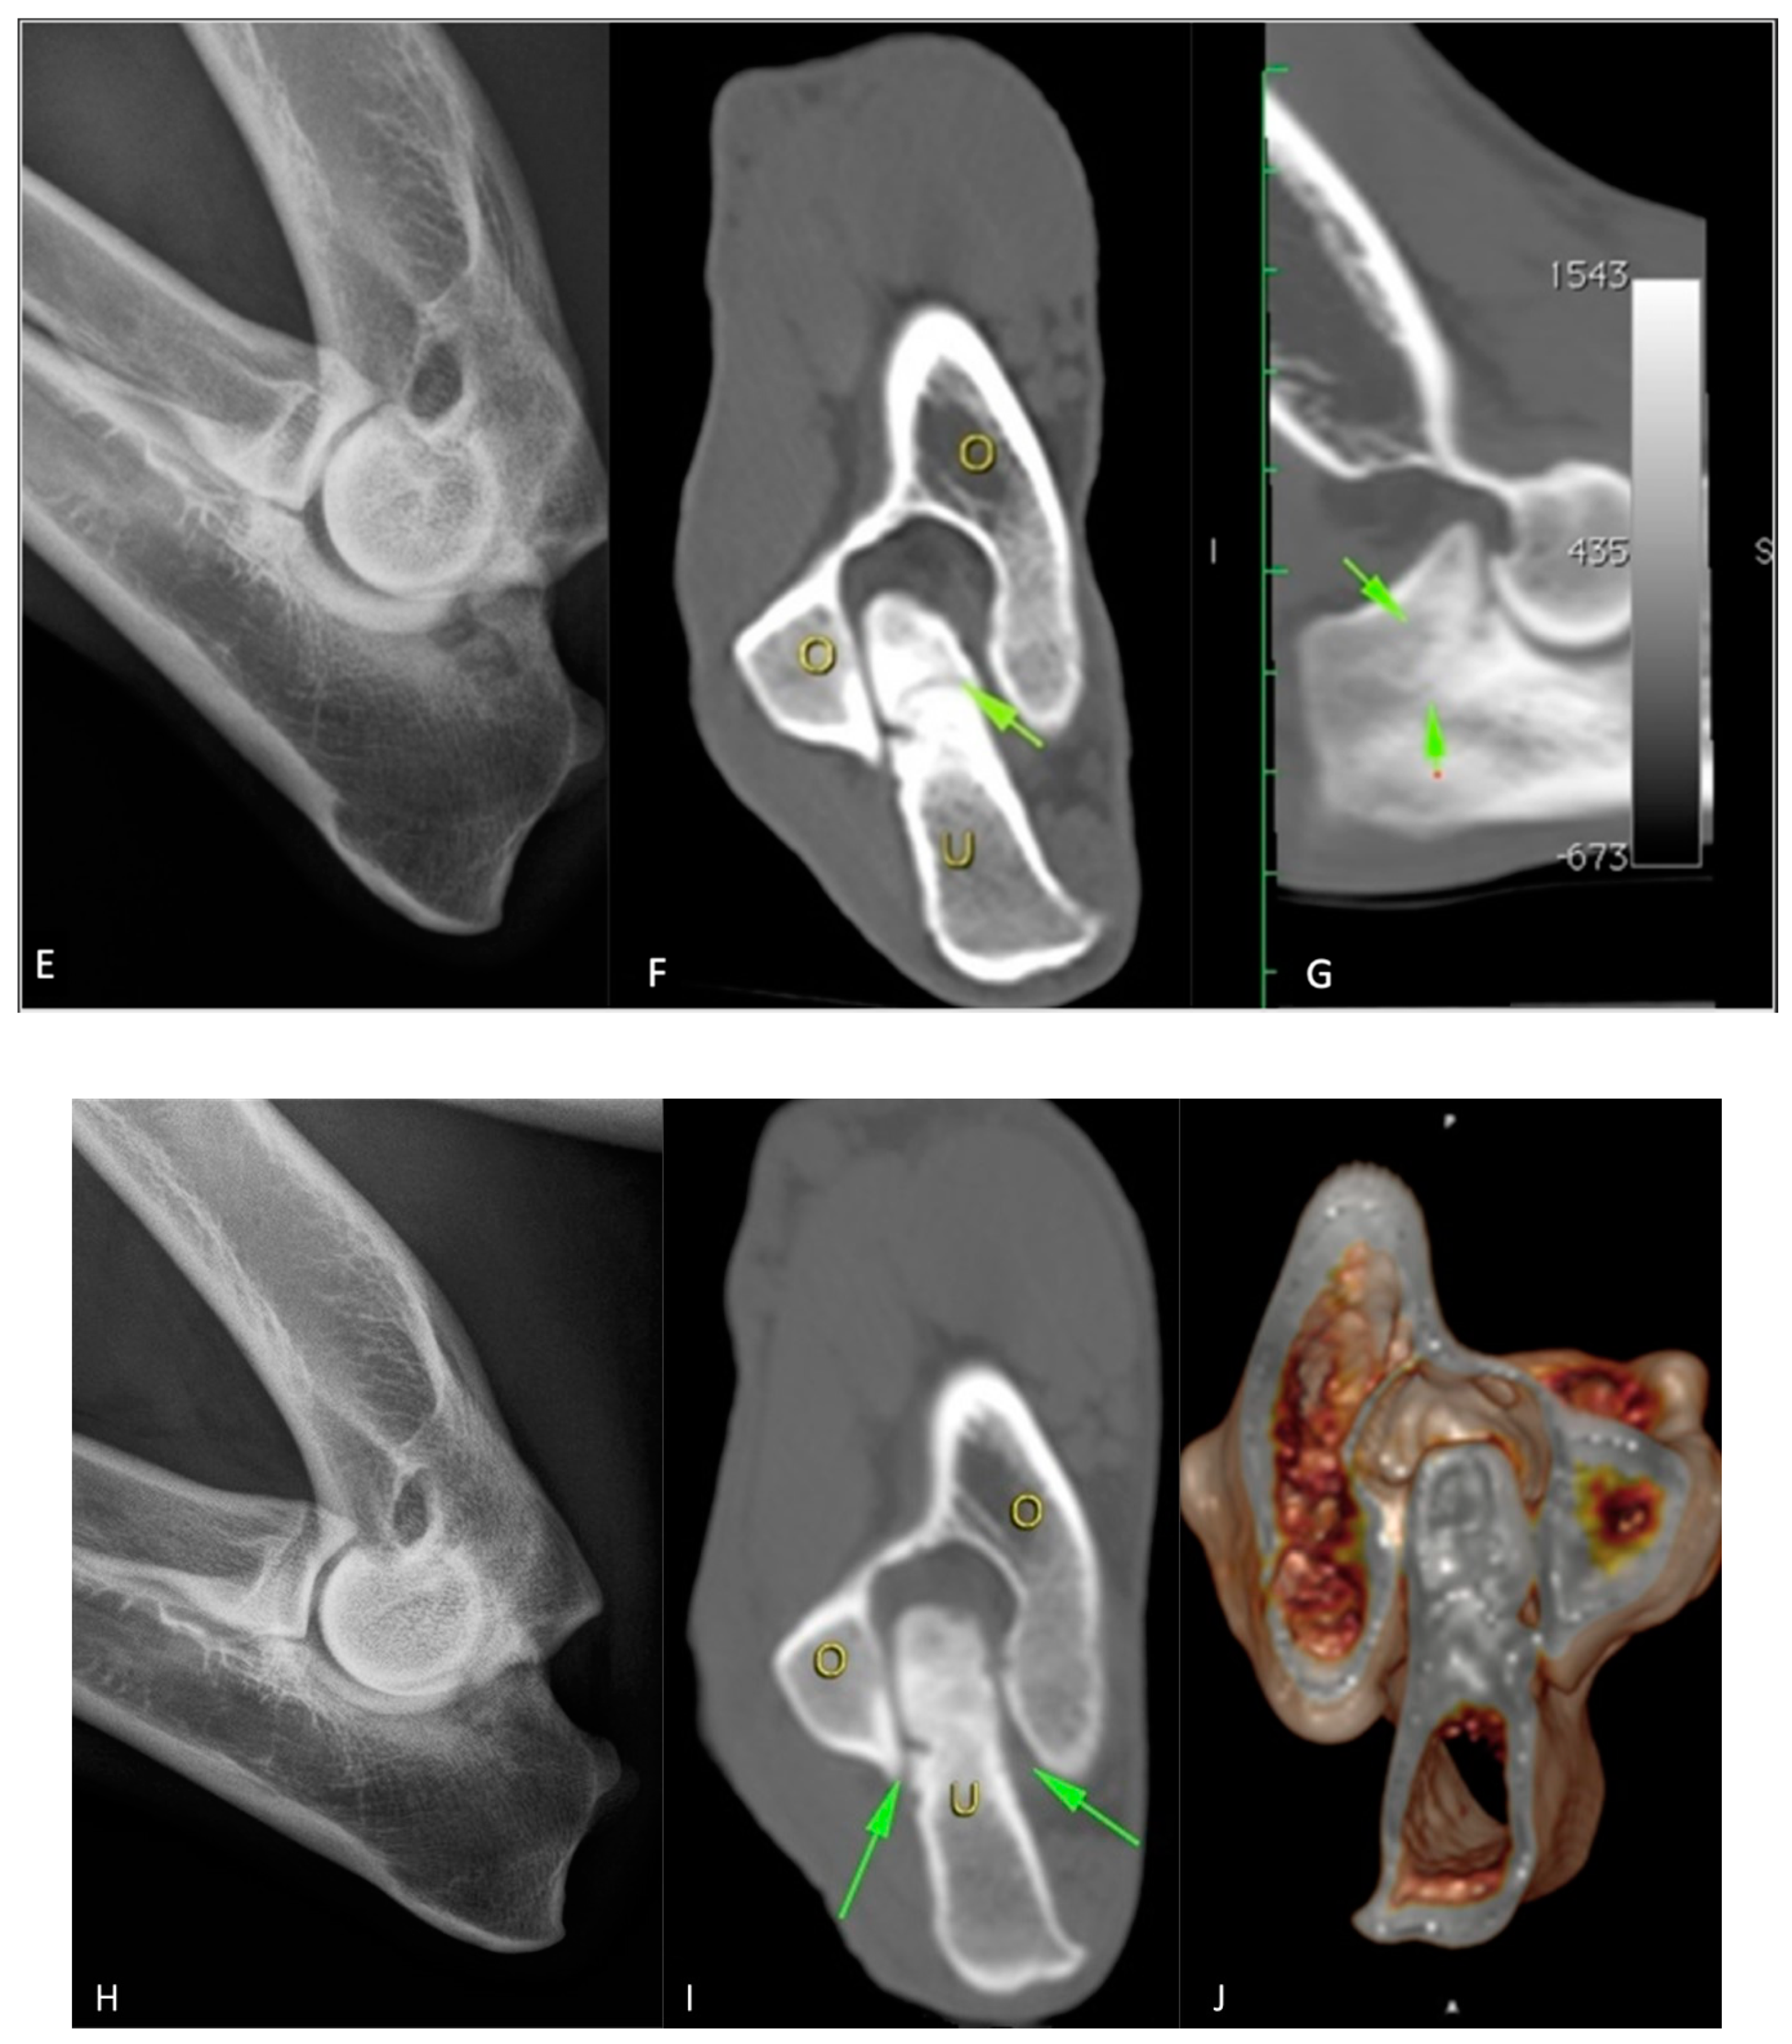

3.1. X-ray Results

3.2. CT Results

3.5. Microradiographic Assessment